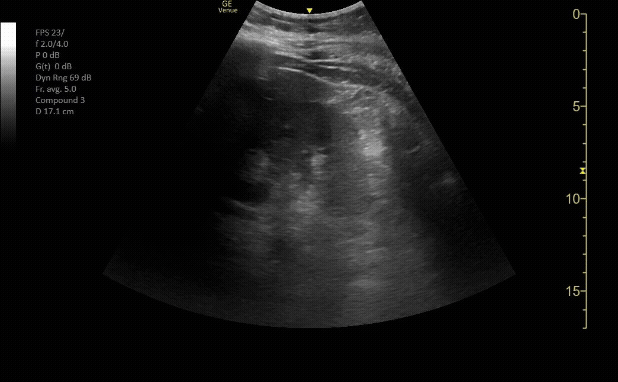

Bladder in transverse view

c/o Erica Dolph, MD